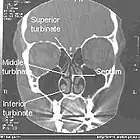

Frontalschnitt einer Computertomographie der Nasenhöhle und Nasennebenhöhle

Frontalschnitt einer Computertomographie der Nasenhöhle und Nasennebenhöhle -